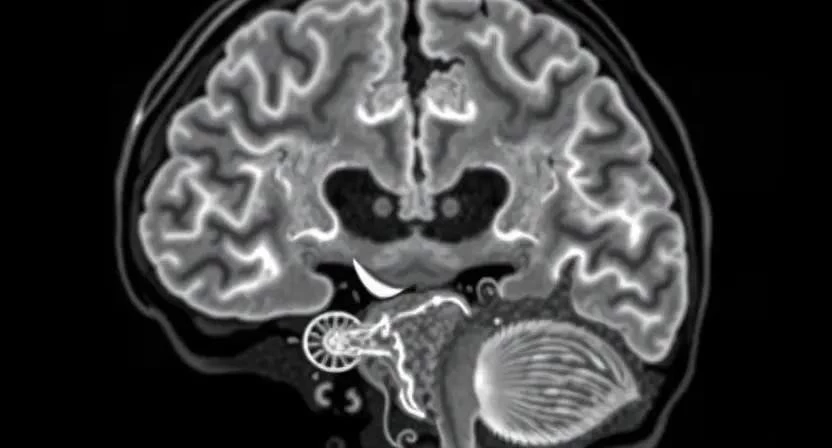

Диагностика инсульта

Диагностика инсульта требует быстрого и точного обследования. Основными методами обследования являются компьютерная томография (КТ) и магнитно-резонансная томография (МРТ) головного мозга. КТ позволяет быстро выявить кровоизлияние в мозг, а МРТ – более точно определить область поражения и тип инсульта. Также проводятся анализы крови для оценки уровня холестерина, сахара и других показателей, которые могут указывать на факторы риска инсульта. Важно как можно быстрее поставить диагноз, чтобы начать лечение в кратчайшие сроки. Врачи должны действовать оперативно, чтобы минимизировать повреждение мозга.